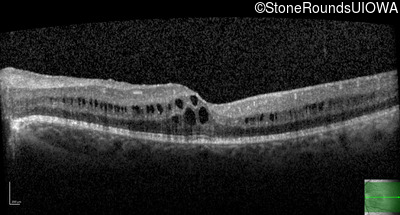

Optical Coherence Tomography - Left - 20/32 -1

Exemplar / OCT Stack